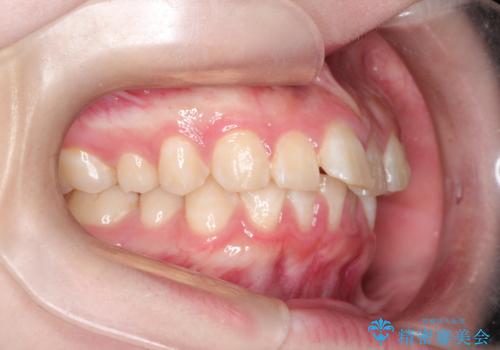

インビザラインで前歯のガタガタをきれいな歯並びへ

- 前歯のガタガタが気になるとのことで来院されました。

上顎の前歯の叢生があったのと、下あごの前歯が通常より1本欠損(先天欠損)していました。

上顎の歯と歯の間をわずかに削りスペースをつくり、並べる計画としました。インビザライン治療を選択されました。

しっかりとインビザラインを使用していただけたので、スムーズに治療を終了させることができました。